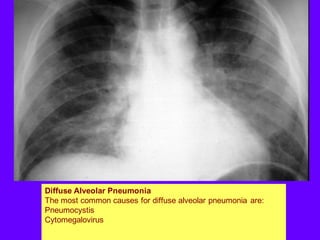

Diffuse Alveolar Pneumonia

The most common causes for diffuse alveolar pneumonia are:

Pneumocystis

Cytomegalovirus